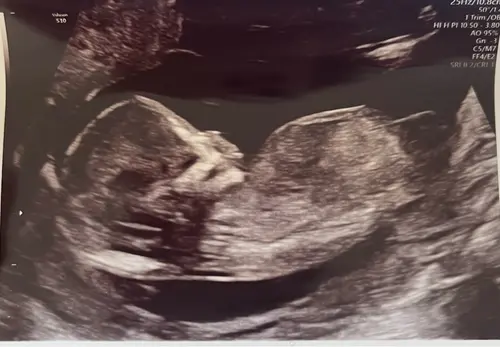

Ik ben heel benieuwd wat jullie hiervan kunnen maken! Het maakt me niet uit wat het wordt, maar ik ben zo enorm nieuwsgierig! Deze echo is gemaakt bij 13 weken en 0 dagen. Hopelijk kunnen jullie er wat theorieën op loslaten! ☺️

Als ik goed naar dit echo-beeld kijk, lijkt de nub wat meer horizontaal/parallel aan de ruggengraat te liggen, niet sterk omhoog gericht. Volgens de NUB-theorie zou dat meer richting meisje wijze